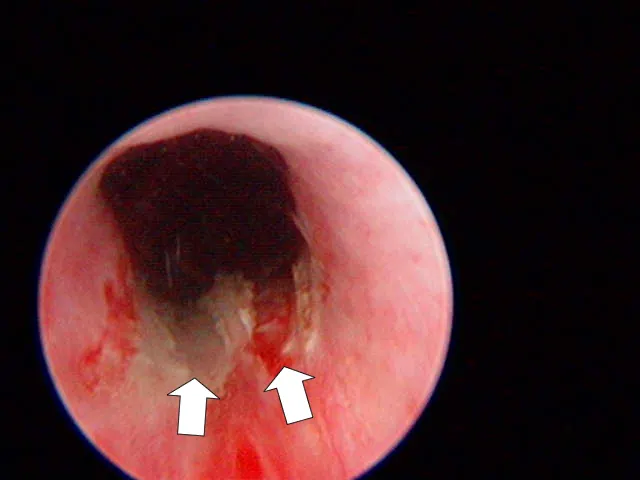

Urinary Endoscopy

An experienced endoscopist can usually identify EUs (Figure 3, arrows; U = urethra lumen).

(Photo courtesy of Dr. John Kruger, Michigan State University)